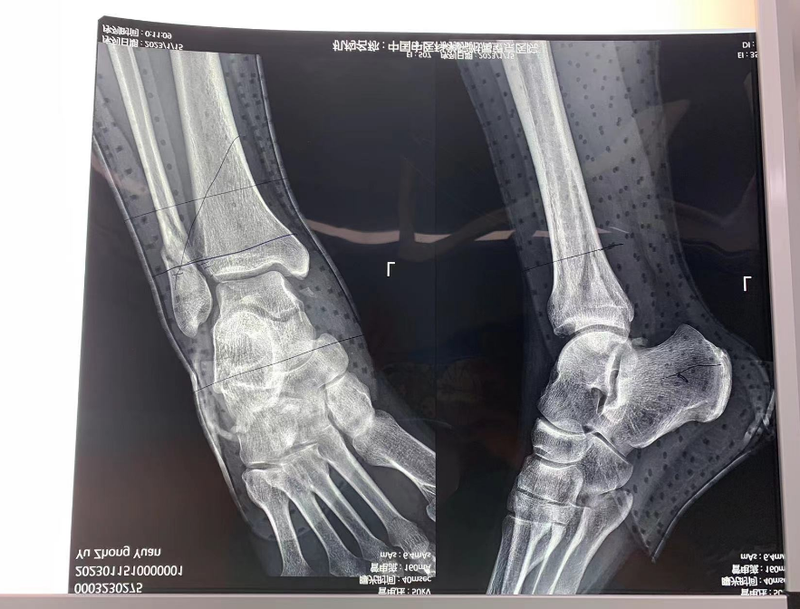

2// 踝关节

本病例由中国中医科学院望京医院骨关二提供(术者:支架主任蒋主任)

【基本资料】患者,男,41岁

本病例踝关节骨折。手术名称:左踝关节骨折外固定支架手术

【治疗前影像】